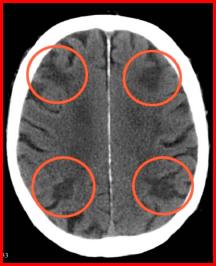

Infarcts due to hypoperfusion are generally located in the watershed areas between the major branches of the cerebral arteries. They occur in cases of prolonged ischemia. In such "low flow" states the areas at the farthest end of the circulatory system become hypoxic and, if the hypoxia is prolonged, undergo infarction. Heart failure, sepsis, and acute blood loss are common causes of watershed injuries to the brain.

Where would you expect hypoperfusion injury to occur? Click the question mark for a hint What other organ in the body is prone to hypoperfusion injury?